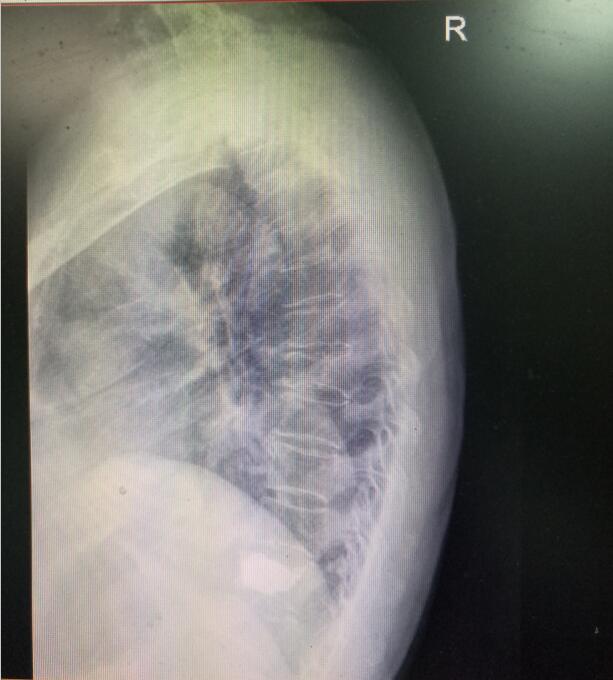

術(shù)前DR(數(shù)字化的x射線)